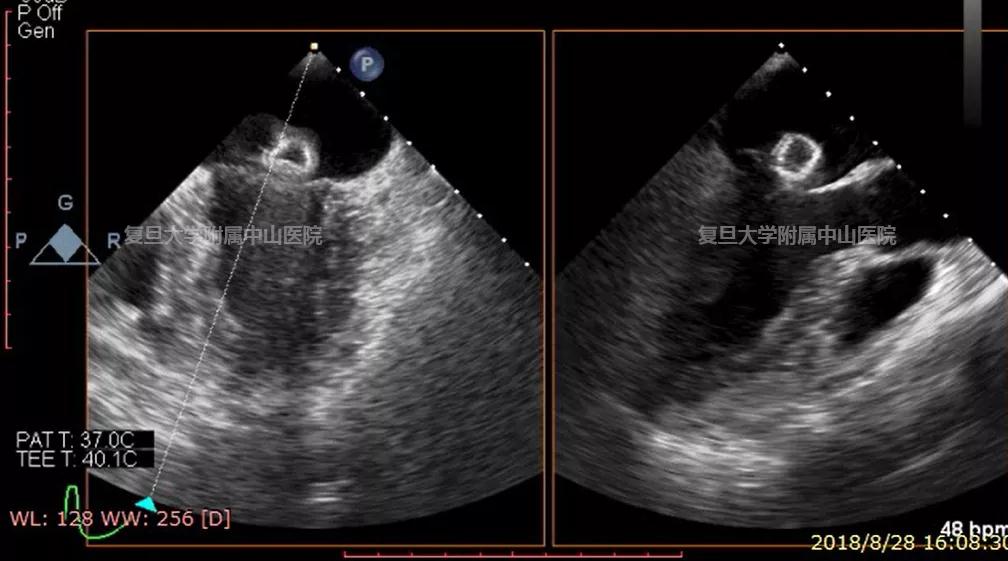

西安西京医院

如图,夹合装置非常准确地定位于二尖瓣瓣口中央,并与二尖瓣闭合线垂直。这么高仿真的肉肉的三维图,宣传委员就偷懒不画解剖对照图了~今天的将心比心给大家介绍了Valve-Clamp经心尖二尖瓣夹合术中超声监测的关键步骤,超人小伙伴们,你们学会了么?敢不敢来挑战一下文末的课后思考题?